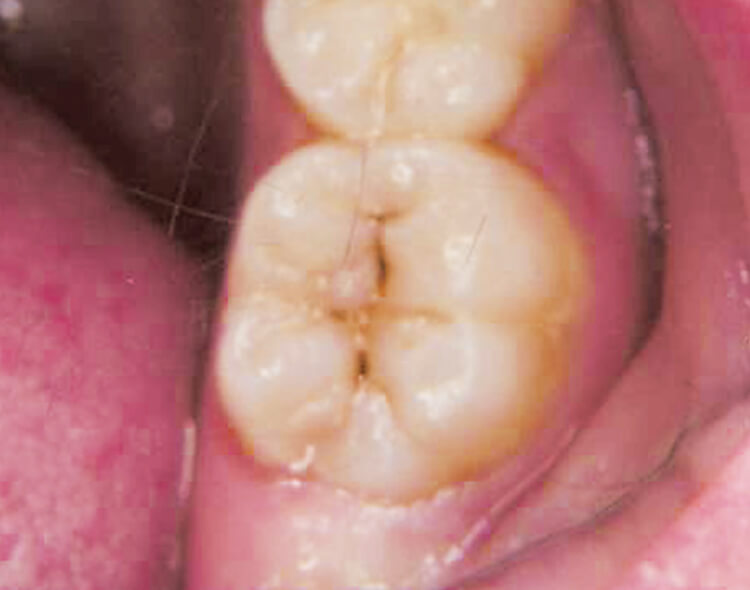

う蝕除去

エナメル小柱の方向が大切で、タービンでの切削とは異なります。チップ先端を小さく動かし、あくまでもチップの照射面を多くするのが勘所です。

10pps250mJ。